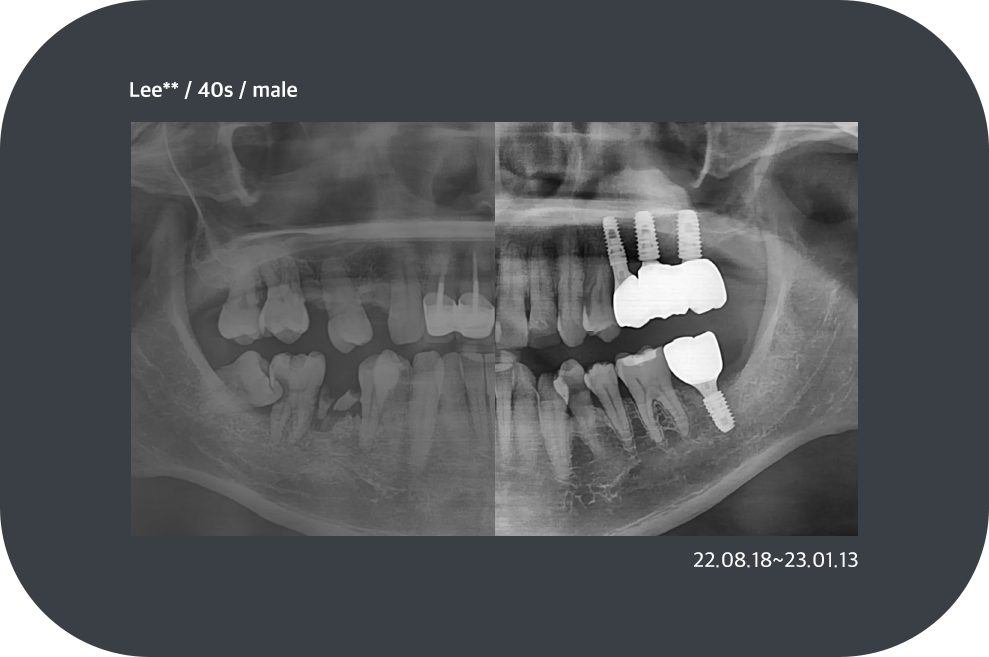

치료사례

임플란트 치료사례

implant_case01

implant_case02

implant_case03

implant_case04

implant_case05

implant_case06

implant_case07

implant_case08

implant_case09

implant_case10

implant_case11

implant_case13

implant_case14

*모든 증례 사진은 의료법 제23조, 제56조에 의거하여, 당사자의 동의하에 게시하였습니다.

*치료 사진은 모두 본원에서 치료한 환자분의 사진입니다.

*치료 사진은 모두 동일인의 사진이며, 동일조건에서 촬영하였습니다.

*개인의 차이에 따라 시술 및 수술 후 부작용이 발생할 수 있으며, 의료진과 충분한 상담을 받으시기 바랍니다.